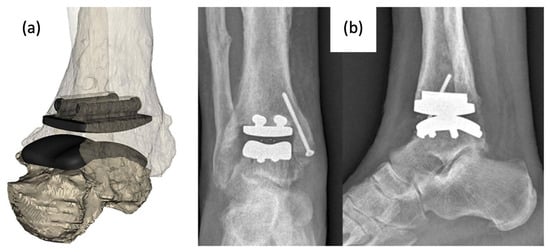

The bone consists of three parts: head, neck, and body. In first-generation TTA implants (Figure 8), the prosthesis consisted of two components: the talar body and a peg for attachment into the talar neck. Only the talar body was replaced, and the talar neck was fixated on the prosthetic stem with bone cement. Satisfactory results were reported in post-operative evaluations, with preserved joint stability and increased mobility of the ankle and foot. However, there were noted issues with prosthesis congruence and prosthesis failure where the prosthesis stem had sunken into the talar neck [,].

Figure 8. (a,b) First-generation talar body prosthesis with an attachment peg and (c,d) second-generation prosthesis [,].

In second-generation TTA implants (Figure 8), the peg was removed to address the previously reported sinkage and subvert the concentration of stress in the talar neck. The talus body was surgically placed without fixation. While radiological appearances were more satisfactory, second-generation implants could not be recommended as a treatment for avascular necrosis due to the high degree of loosening seen between the prosthesis and talar neck [].